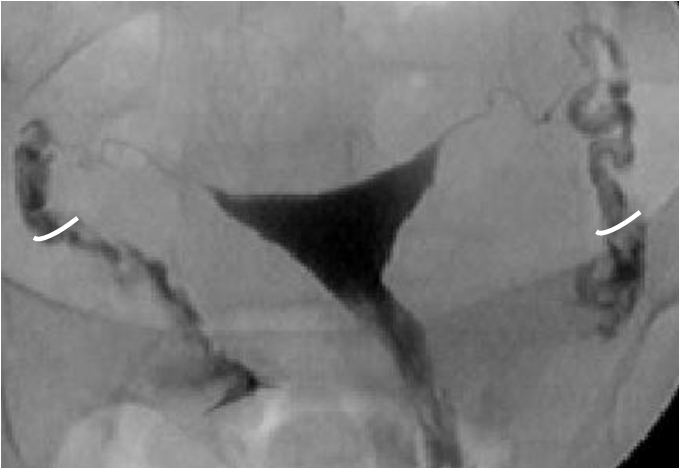

Histerosalpingografi (HSG) veya Türkçe deyişle rahim filmi jinekolojide rahim içinin ve kanalların yapısal ve işlevsel özelliklerini incelemede kullanılan bir yöntemdir. İnfertilite (kısırlık) değerlendirmesinde istenen temel testlerden birisidir. Yandaki resimde normal bir rahim şekli ve her iki kanaldan ilacın kolayca geçip karın boşluğuna dağıldığı normal bir film görülmektedir. Ayrıca rahim ağzına veya rahme uygulanan bir müdahale sonrasında (kürtaj gibi) adet kanamalarının kesilmesi ya da çok azalması durumunda rahim ağzı kanalındaki muhtemel bir tıkanıklığın veya rahim içersindeki muhtemel bir yapışıklığın (Asherman sendromu) değerlendirilmesinde, tekrarlayan düşüklerde rahimde doğumsal bir gelişim kusuru bulunup bulunmadığının (aşağıda soldaki resim - bölmeli rahim) belirlenmesinde de yaygın olarak kullanılır.